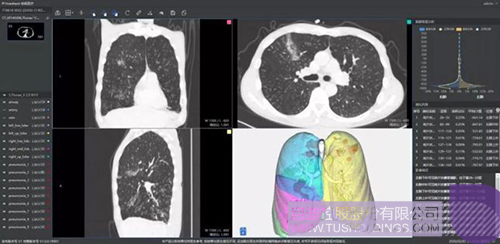

柏視醫(yī)療

推出的新冠肺炎輔助篩查系統(tǒng)借助AI技術(shù)可行之有效地輔助大規(guī)模新冠肺炎病例的影像篩查工作。同時(shí)基于肺部結(jié)構(gòu)快速智能分割,讓醫(yī)生對肺部病變情況一目了然。還可結(jié)合臨床征象,自動生成符合最新型冠狀病毒指南的結(jié)構(gòu)化圖文報(bào)告,輔助醫(yī)生大幅提升診斷效率,同時(shí)提高診斷準(zhǔn)確性。